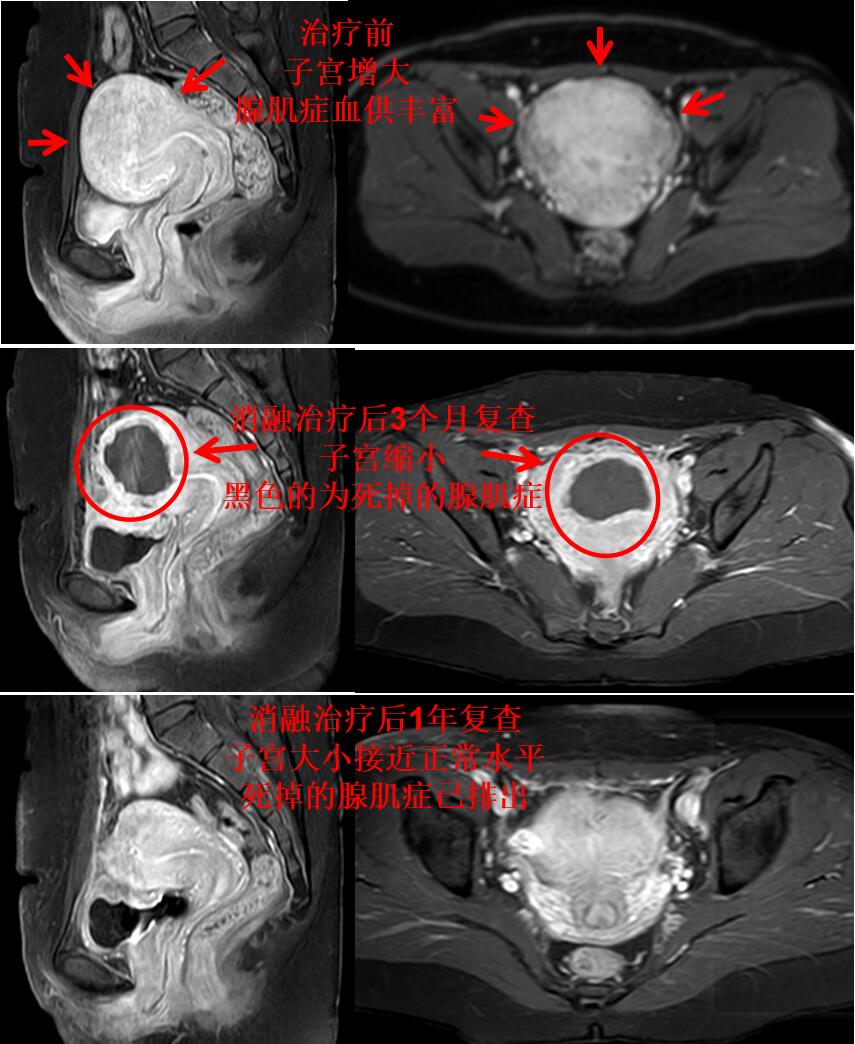

门诊磁共振检查:子宫明显增大(10.5*9.3*7.2cm3),子宫腺肌症,以左侧壁、宫底及后壁明显(如下图)。

下图为栓塞治疗前子宫腺肌症病灶的血供丰富,栓塞治疗后腺肌症血管堵塞,腺肌症灭亡。

介入微创栓塞治疗后无痛经,3个月复查的磁共振:子宫腺肌症完全灭亡,无血流,子宫缩小,治疗前后对比如下图。

李女士治疗后满1年,痛经没有复发。下图为治疗后1年复查的磁共振图(子宫腺肌症完全灭亡,子宫基本正常(与没有腺肌症的正常妇女的子宫相仿))。